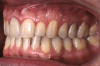

Fig 18. Bite interdigitation to finalize surgical orthodontic correction. After orthodontics, periodontal plastic surgery, bleaching, microabrasion, and restorative dentistry were performed.

Fig 19. Bite interdigitation to finalize surgical orthodontic correction. After orthodontics, periodontal plastic surgery, bleaching, microabrasion, and restorative dentistry were performed.

Fig 20. Bite interdigitation to finalize surgical orthodontic correction. After orthodontics, periodontal plastic surgery, bleaching, microabrasion, and restorative dentistry were performed.